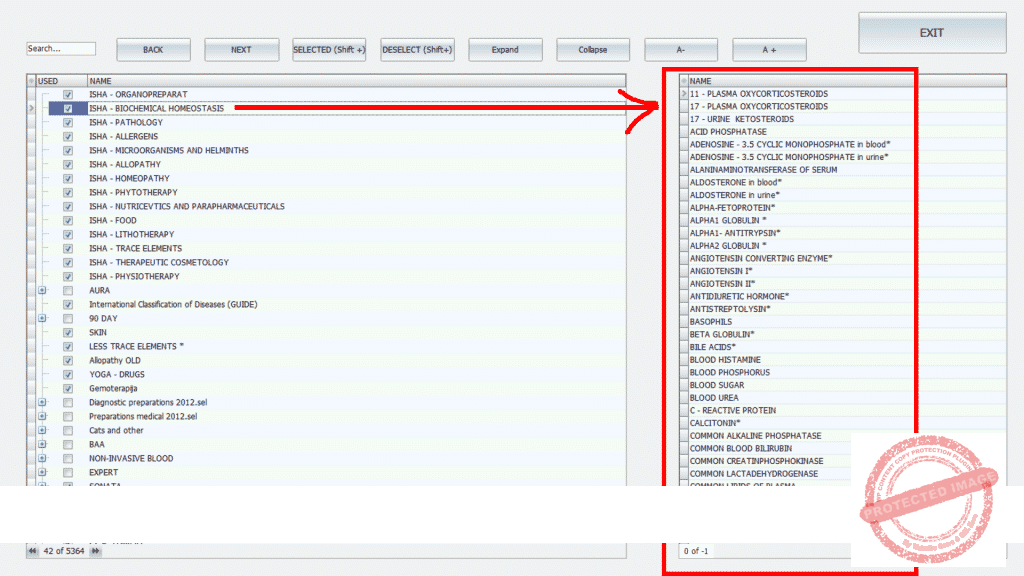

A preview of The ISHA META Human 5000+ software with over 5000 libraries etalons ![]()

+ 5000 etalons / libraries /catalogswith over 100.000 remedies, liboratoria , healing modalities !